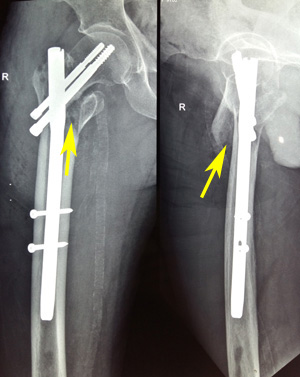

Figure 1a Varus reduction as demonstrated by medial overlap of fragments (thin arrow). Also note lateralization of entry point (thick arrow).

Figure 1b Manipulation with Steinmann pin to correct neck shaft angle as demonstrated by medial continuity and correction of overlap (arrow).